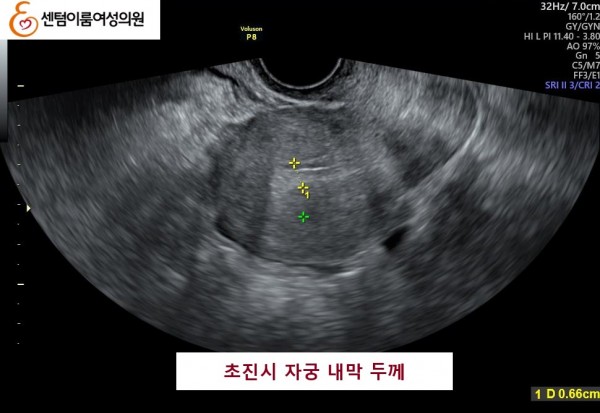

2024.12월 본원 내원시 오른쪽 난소에 자궁 내막증이 있었고, 자궁 내막 또한 얇았습니다.

오른쪽 난소 알콜 경화술을 통하여 내막증을 치료 후, 자연 임신에 성공 하셨습니다.